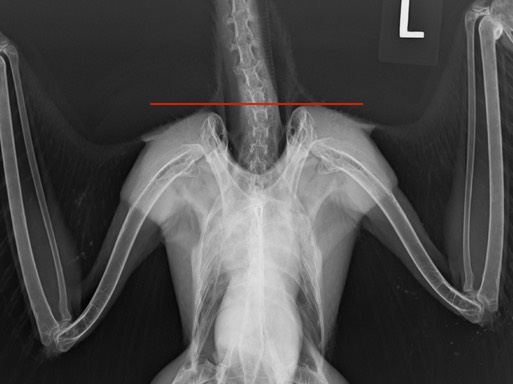

Cooper’s Hawks hunt other birds. If you feed songbirds in your yard, you may also attract a Cooper’s Hawk. A common cause of injury in Cooper’s Hawks is collision with a window, often while chasing prey. 21-014 flew into a window at a Kennewick Fire Station, injuring her right shoulder. If you look at the horizontal line in the radiograph below you will notice that the right shoulder is lightly lower than the left shoulder. The upper arrows are pointing at the top of the scapulas. The right scapula is lower than the left scapula. The bottom arrows are pointing at the base of the coracoids where they attach to the sternum. The right coracoid is dislocated and lower than the left coracoid.

Coracoid fractures and dislocations are a fairly common shoulder injury. There are currently five other birds recovering from coracoid injuries at BMW: another Cooper’s Hawk, a Red-tailed Hawk, a Barn Owl, a Great Horned Owl and a Bald Eagle.